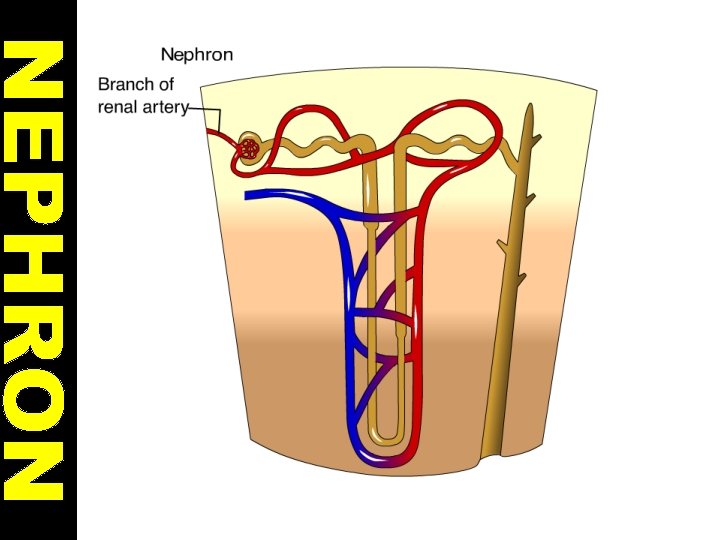

STRUCTURE OF KIDNEY 1. Cortex: It contains glomerulus and Bowman’s capsules. 2. Renal Capsule: It surrounds and protects the kidneys.

3. Medulla: It is located under the cortex and has malphigian pyramids. Malphigian pyramids contains urine collecting canal and loop of henle. 4. Pelvis: It is innermost part of kidney. The urine is collected in pelvis.

NEPHRONS • They are structural unit of kidneys. • A nephron begins with a glomerulus. • Glomerulus is surrounded by a Bowman’s capsule. • Each glomerulus is formed by capillaries from a branch of renal arteriole.

• The complex of Bowman’s capsule and glomerulus is called malpighian body. Bowman’s capsule is connected with long tubule that is called Loop of Henle. • Loop of Henle is joined with collecting duct.

FILTRATION • During filtration, substances pass from the blood into the Bowman’s capsule. • Under pressure, water and many small molecules such as salts, urea, glucose and aminoacids pass from glomerulus into Bowman’s capsule.

REABSORBTION • The absorbtion of needed materials such as glucose, amino acids and water from nephrons to blood capillaries is called reabsorbtion. • Water is reabsorbed passively by osmosis. But reabsorbtion of glucose, aminoacids and salt ions occurs by active transport.

• All glucose, aminoacids and many salt ions are reabsorb during reabsorption. • Most reabsorbtion takes places in loop of henle. • Antidiuretic hormone (ADH or Vasopressin) regulates concentration of water in blood. • It increases water permeablity of the cells of the distal tubules.